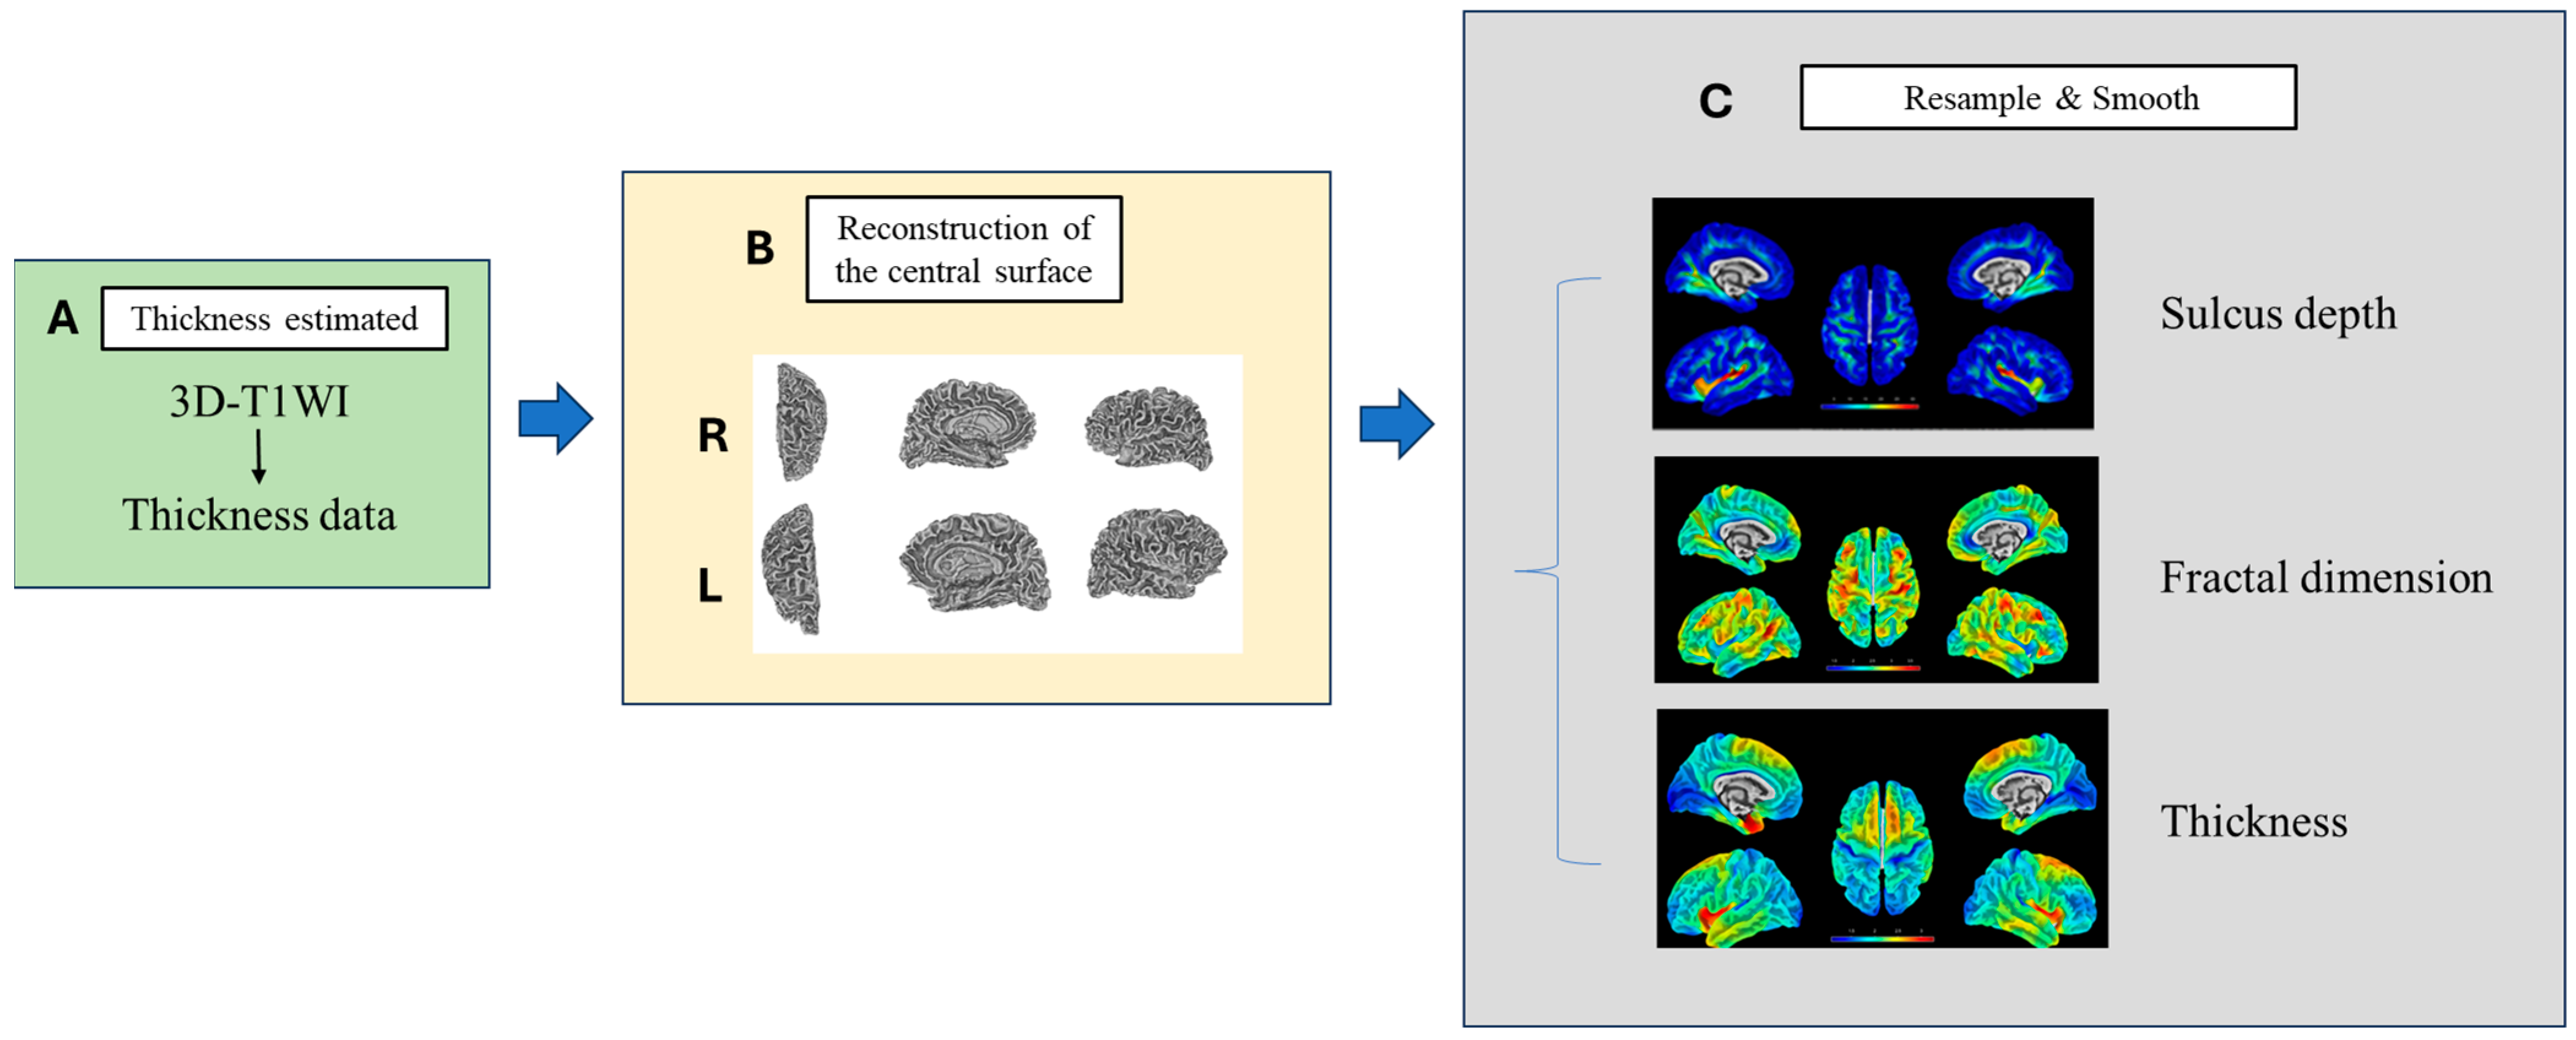

2.5.2. High-Resolution 3D-T1WI Image